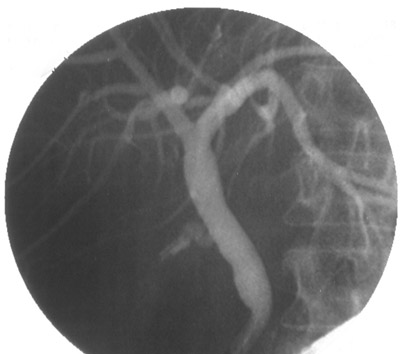

![]() | This radiograph was taken at the time of an endoscopic retrograde pancreatography (ERCP) procedure and the common bile duct is outlined along with the right hepatic duct and the left hepatic duct. No obstruction is present in this case. However, note the stump of the cystic duct from a previous cholecystectomy. |